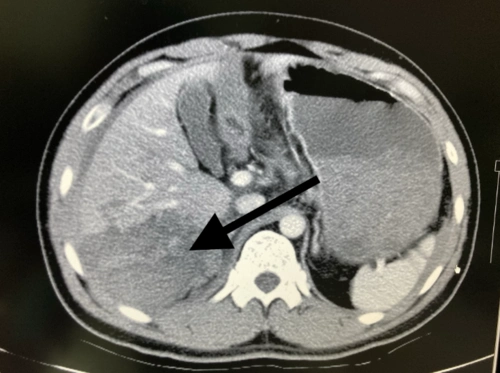

险南平一小伙醉酒不慎摔了一跤致肝破裂医生死亡率高达80以上